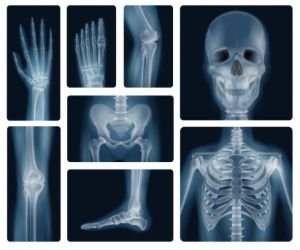

Radiografía de huesos.

- Mano.

- Muñeca.

- Brazo.

- Codo.

- Hombro.

- Columna.

- Pelvis.

- Cadera.

- Muslo.

- Rodilla.

- Pierna (espinilla).

- Tobillo o pie.